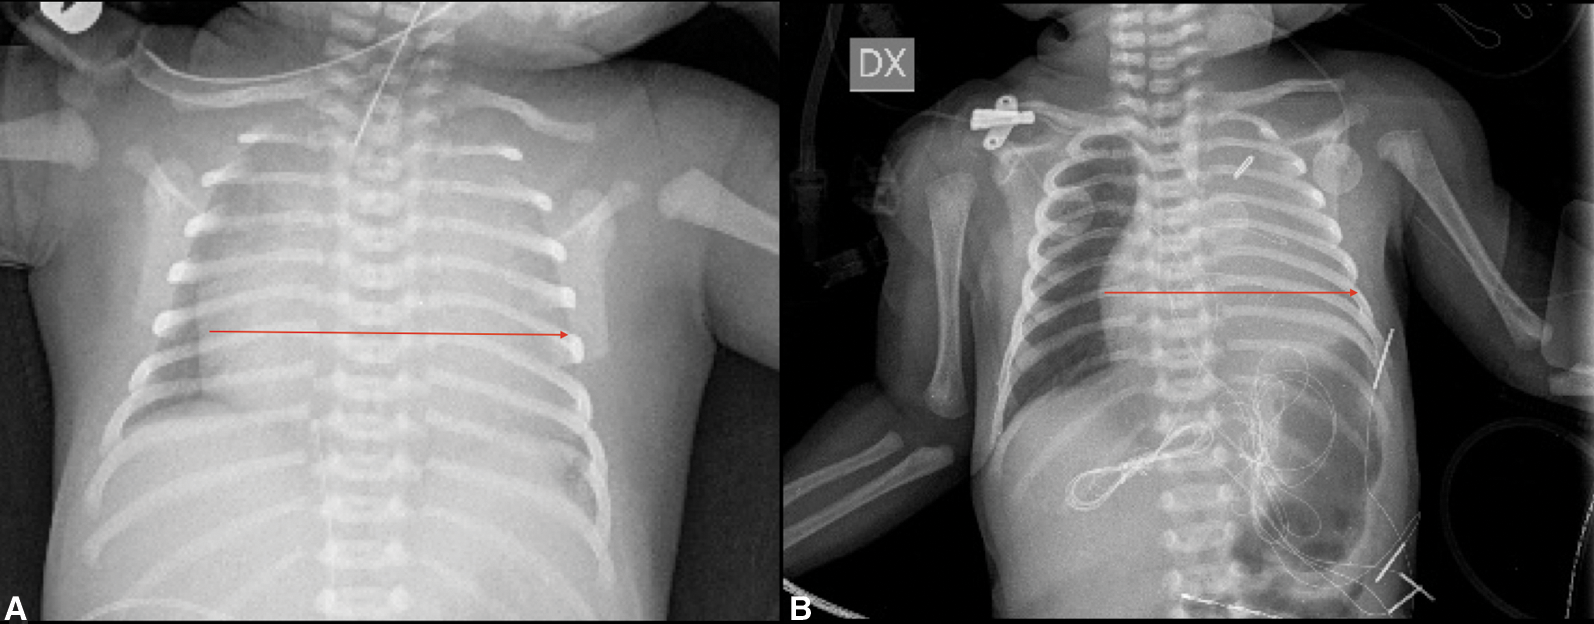

High intravenous dosage of Prostaglandin E1 (PGE1) was administered immediately. Chest X-ray showed severe cardiomegaly and wall to wall heart (Fig. 3A). After diuretic and dopamine therapy, TR improved from severe to trivial, but persisted functional PA with a thickened non-opening pulmonary valve without anterograde flow. Multidisciplinary team decision was to progressively reduce Prostaglandin’s dose and clinical observation. Clinical conditions progressively worsened with an imposing right heart failure characterized by ascites, hepatomegaly and anuria (creatinine: 2 mg/dl). Despite diuretic therapy and paracentesis drainage, we faced with further deterioration of clinical conditions such as increase lactates levels (6.5 mmol/l) and lower peripheral oxygen saturation of 75%. Serial echocardiograms documented persistence of a large PDA and limited opening of the pulmonic valve cusps, with initial mild anterograde flow. After 5 days of ineffective Ibuprofen administration, surgical PDA ligation was indicated and performed (Fig. 4). By sternotomy approach the first surgical findings were the evidence of cardiomegaly (Fig. 5) and a very large PDA that was ligated. Immediately after the procedure, progressive reduction of the right chambers’ enlargement and oxygen saturation improvement (up to 95%) was noted. Intraoperatory transesophageal echocardiography showed normal opening of the pulmonary valve and persistence of trivial tricuspid valve regurgitation.

Since right heart failure completely regressed three days after the procedure and heart size at chest X-ray markedly improved (Fig. 3B), we speculate that surgical PDA closure relieved “competitive” anterograde pulmonary blood flow with consequent decompression of the RV.

Figure 3: Chest X-ray (A) Red arrow: Wall to wall heart pre surgery (B) Red arrow: Heart dimension post-surgery